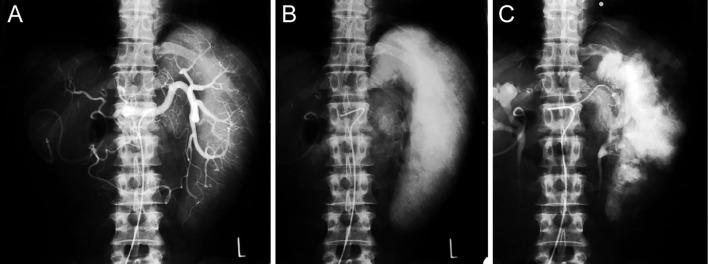

A 53-year-old male patient with a history of hepatocellular carcinoma developed gastroesophageal varices refractory to endoscopic injection sclerotherapy (EIS). He required EIS six times in 2 years for recurring variceal bleeding. After hepatic resection, he developed massive splenomegaly. Partial splenic embolization (PSE) was performed to reduce the portal pressure. Varices and variceal bleeding were not detected during 13-year follow up, until the patient died of hepatocellular carcinoma. This is a unique case of gastroesophageal varices controlled by PSE and improved portal hypertension.

一名有肝细胞癌病史的53岁男性患者出现了对内镜注射硬化疗法(EIS)难治的胃食管静脉曲张。他在2年内因复发性静脉曲张出血接受了6次EIS治疗。肝切除术后,他出现了巨脾。进行了部分脾栓塞术(PSE)以降低门静脉压力。在13年的随访期间未检测到静脉曲张和静脉曲张出血,直到患者死于肝细胞癌。这是一例通过PSE控制胃食管静脉曲张并改善门静脉高压的独特病例。